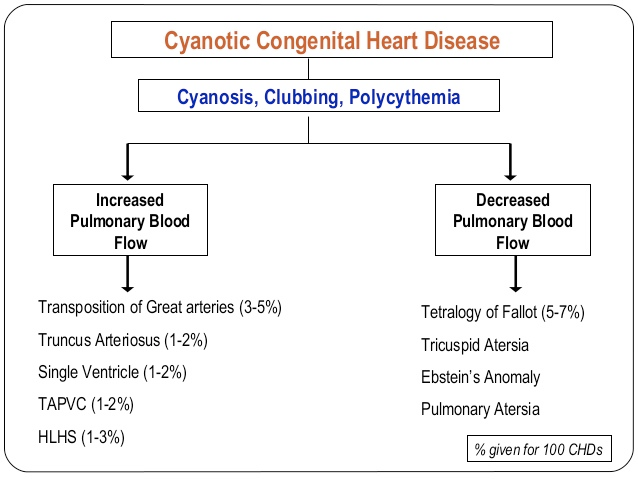

Causes de Cyanose centrale

Les 5.5 T

- Tetralogie de Fallot

- Transposition des Gros vaisseaux

- Truncus Arteriosus (tronc artériel Commun)

- Total Anomalus Pulmonary Venous Return (TAPVR)

- Tricuspid Valve abnormalities (Ebstein, Atresie Tricuspide)

Celles avec Flux pulmonaire diminué = Celles avec atrésies du système droit